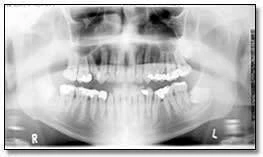

Hình ảnh thể hiện mức độ tiếp xúc quá mức có thể dẫn đến việc không phát hiện được các đặc điểm bệnh lý. Hình 34a là phiên bản nâng cao kỹ thuật số của bức ảnh 34b. Có thể thấy Hình 34b bị phơi sáng quá mức khi chụp, thể hiện rõ ràng sự xuất hiện của một vùng bức xạ gây ra sự mở rộng và mỏng đi của phần xương bên dưới của hàm phải – những đặc điểm không thể hiện rõ trên bản gốc.

Ví dụ về hình ảnh toàn cảnh thiếu sáng

Hình ảnh với liều tia không đủ có thể dẫn đến không phát hiện được các đặc điểm bệnh lý. Hình 35a là một phiên bản nâng cao kỹ thuật số. Chúng ta có thể dễ dàng thấy chiếc răng hàm thứ ba bên phải bị tác động mà bị mờ đi trên bản gốc. Sự tăng cường này cũng chứng tỏ rõ ràng bệnh nhân có một bệnh lý liên quan đến răng hàm dưới thứ hai bên phải.